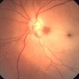

- central retinal artery occlusion (CRAO), cherry red spot

- Imaging device

- Fundus camera

- CRAO with arterial narrowing, disc pallor,retinal edema, cherry red spot and plaques in the inferonasal artery; notice the choroidal nevus in superonasal retina.